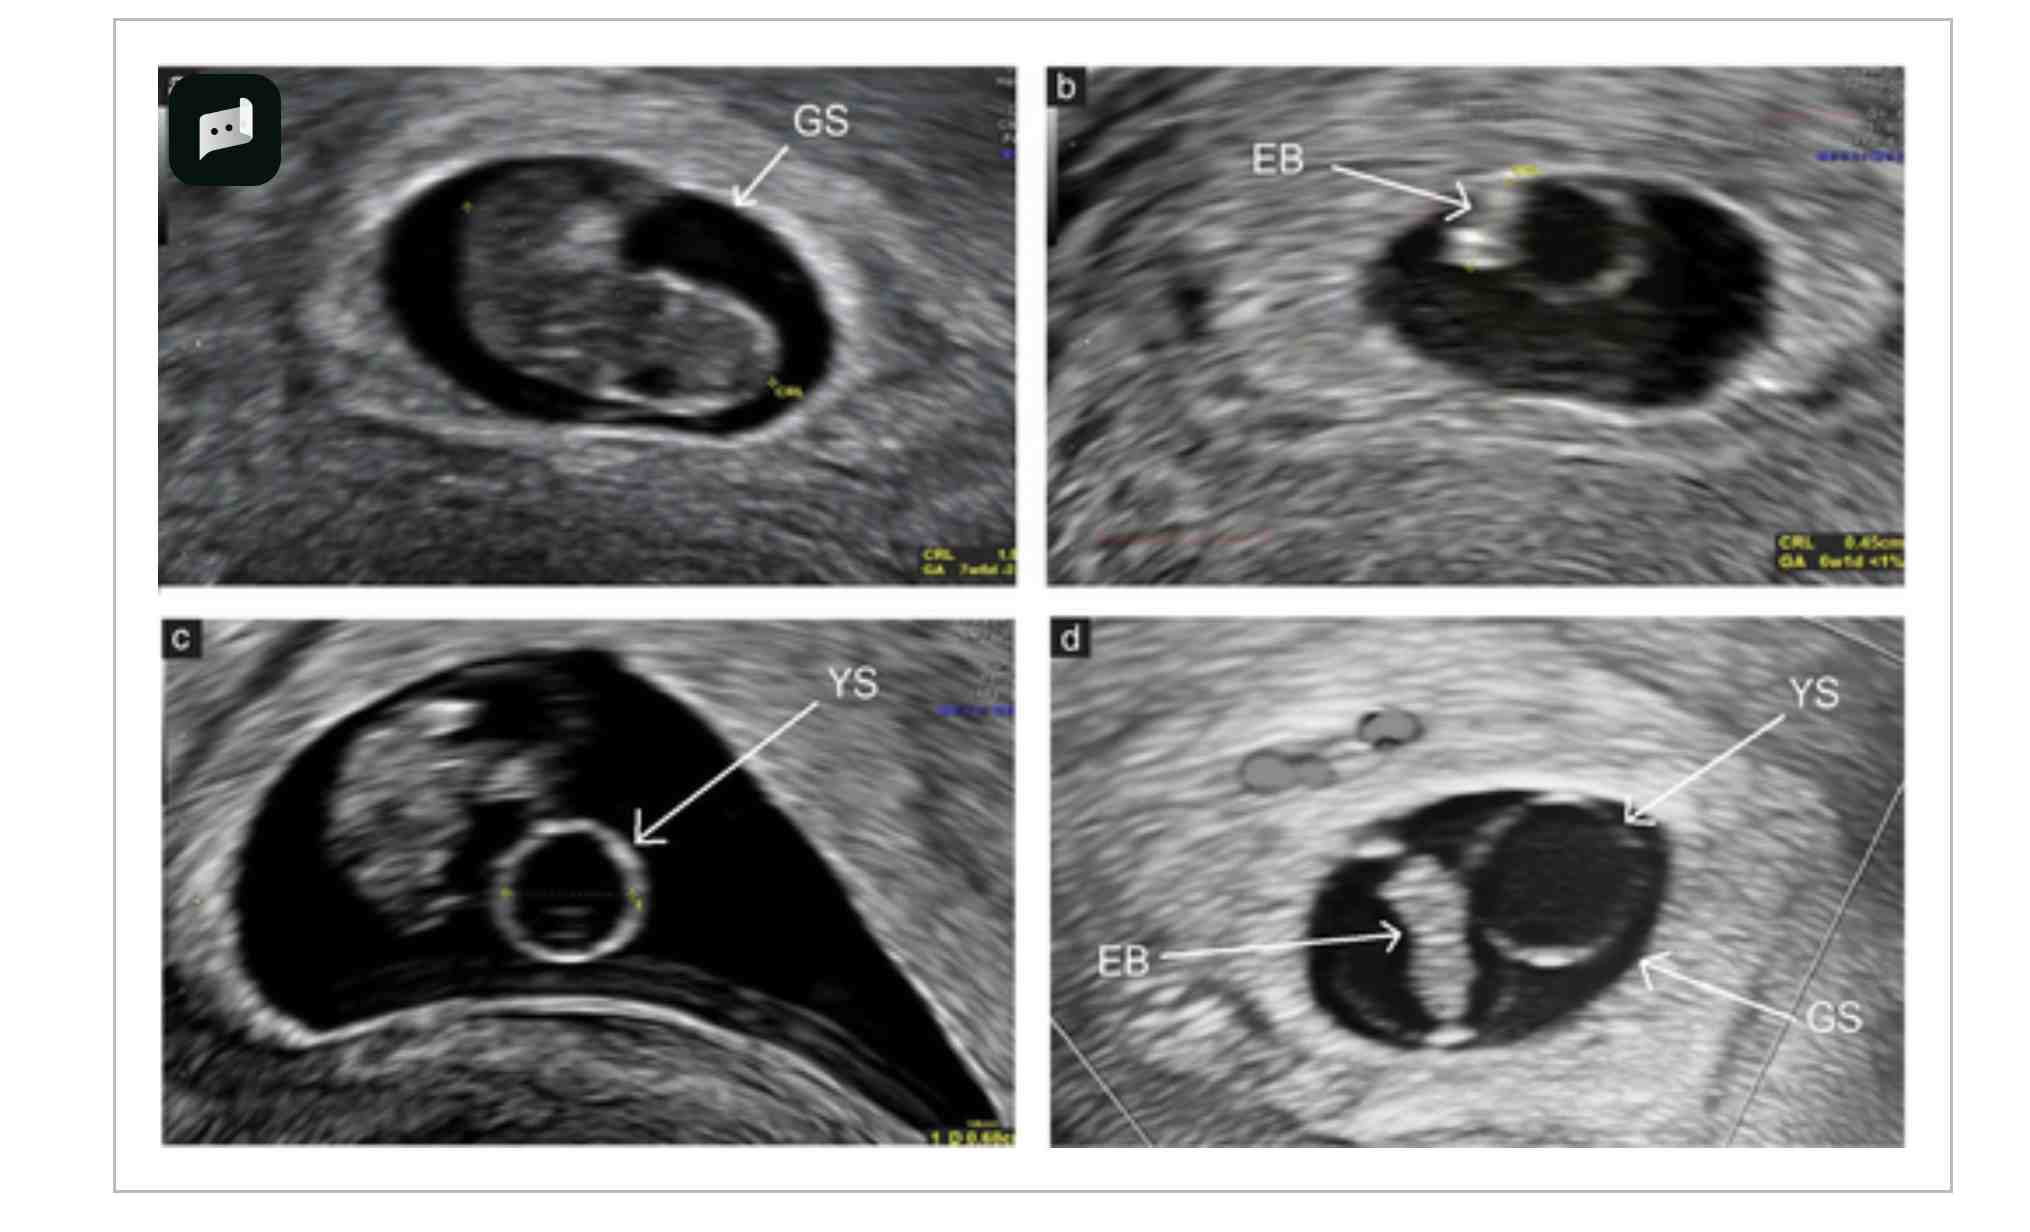

根据预先定义的超声形态学异常的存在情况,对异常核型的概率进行了评估,包括单独存在和合并存在两种情况(表3)。单独评估时,在所有孕龄中,每个异常超声特征都与异常核型显著相关,其中CRL<第5百分位数的OR最高(5.51(95%CI,2.53-12.01);P<0.001)。合并评估时,非整倍体四联征(GSMD<第5百分位数+YSMD>第95百分位数+CRL<第5百分位数+心动过缓)与异常核型显著相关,特别是在检查时间<10周的病例中(OR,7.51(95%CI,2.41-140.22);P<0.001)。TVS显示的异常形态学发现的超声图像见图3。